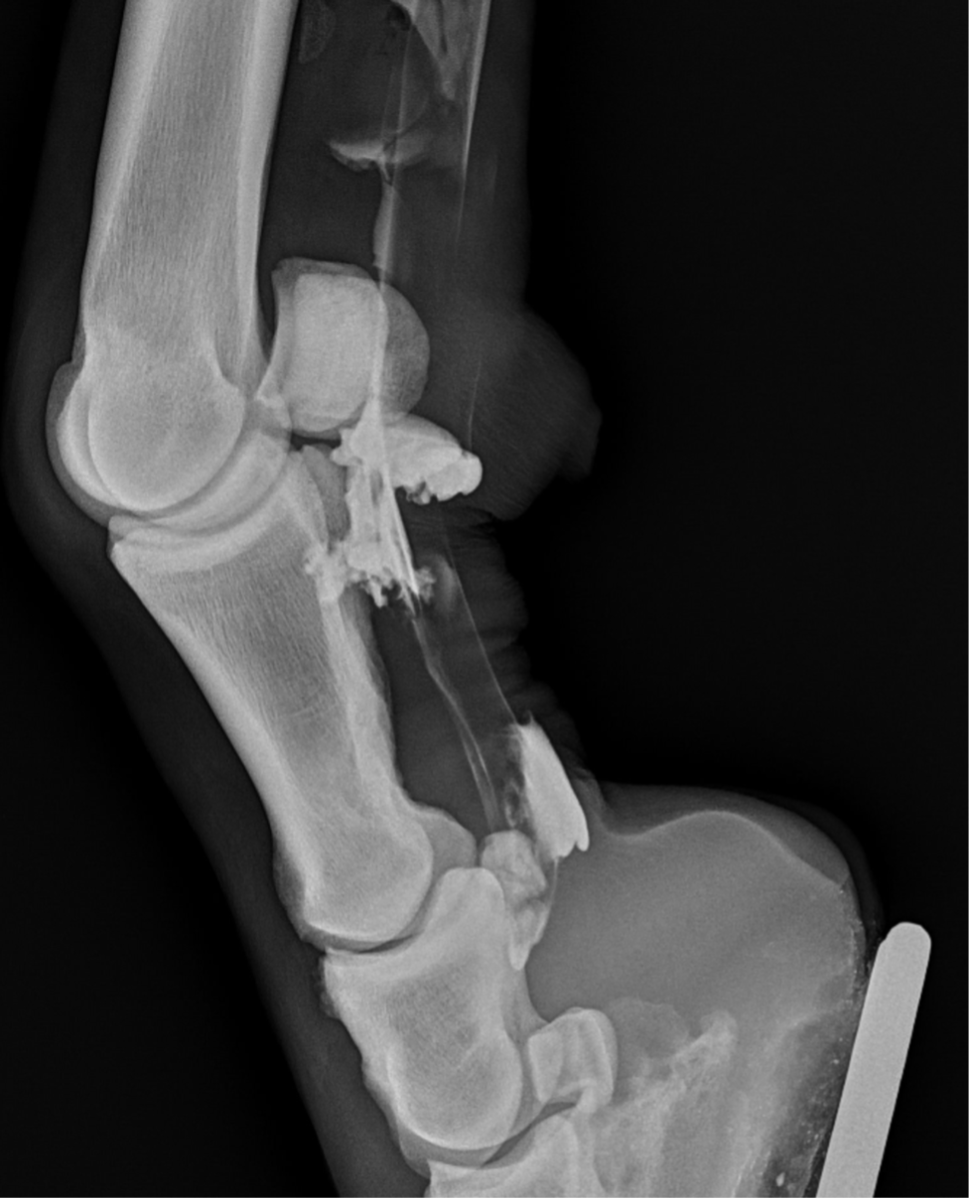

A Star Performer: 12-Year-Old Showjumping Crossbred Gelding

In this case report we look at a 12-year-old crossbred gelding who show jumps competitively to 1.40m.

Recently, the gelding developed acute tenosynovitis of the left hind digital flexor tendon sheath (DFTS) following a competition. Despite the owner’s efforts, which included icing, wrapping, and confinement for seven days, there was no improvement in the effusion of the DFTS.

Upon further examination, contrast radiographs and ultrasound scans failed to identify any significant abnormalities apart from swollen synovium within the DFTS. To address this issue, our veterinary team administered 5mg of triamcinolone acetonide along with 20mg of HA, complemented by a compression wrap. Subsequently, the horse underwent a two-week confinement period in a small yard, followed by gradual reintroduction to exercise through 10 minutes of hand walking twice daily, with the distal limb wrapped for additional support.